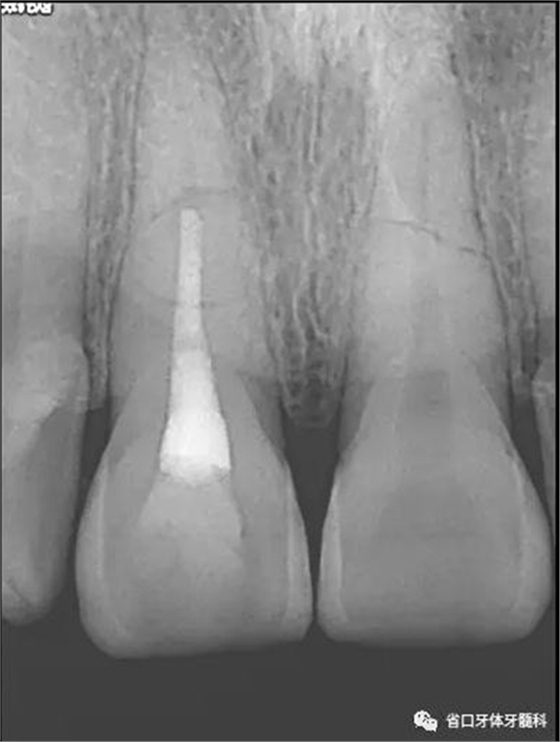

X線片:11、21根中段見橫行根折線,無移位,根尖無明顯異常。

圖2 術(shù)前根尖片